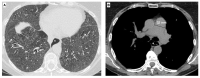

Systemic sclerosis (SSc) is a complex autoimmune disease characterized by significant fibrosis of the skin and internal organs, with the main involvement of the lungs, kidneys, heart, esophagus, and intestines. SSc is also characterized by macro- and microvascular damage with reduced peripheral blood perfusion. Several studies have reported more than 240 pathways and numerous dysregulation proteins, giving insight into how the field of biomarkers in SSc is still extremely complex and evolving. Antinuclear antibodies (ANA) are present in more than 90% of SSc patients, and anti-centromere and anti-topoisomerase I antibodies are considered classic biomarkers with precise clinical features. Recent studies have reported that trans-forming growth factor β (TGF-β) plays a central role in the fibrotic process. In addition, interferon regulatory factor 5 (IRF5), interleukin receptor-associated kinase-1 (IRAK-1), connective tissue growth factor (CTGF), transducer and activator of transcription signal 4 (STAT4), pyrin-containing domain 1 (NLRP1), as well as genetic factors, including DRB1 alleles, are implicated in SSc damage. Several interleukins (e.g., IL-1, IL-6, IL-10, IL-17, IL-22, and IL-35) and chemokines (e.g., CCL 2, 5, 23, and CXC 9, 10, 16) are elevated in SSc. While adiponectin and maresin 1 are reduced in patients with SSc, biomarkers are important in research but will be increasingly so in the diagnosis and therapeutic approach to SSc. This review aims to present and highlight the various biomarker molecules, pathways, and receptors involved in the pathology of SSc.